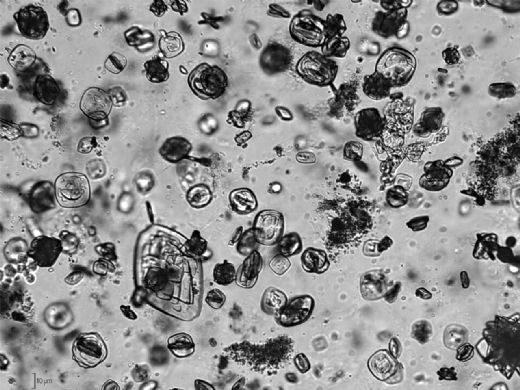

Fosforlu Yeşil İdrarın Olası Nedenleri Fosforlu yeşil renkte idrar, genellikle aşağıdaki durumlarla ilişkilendirilebilir: